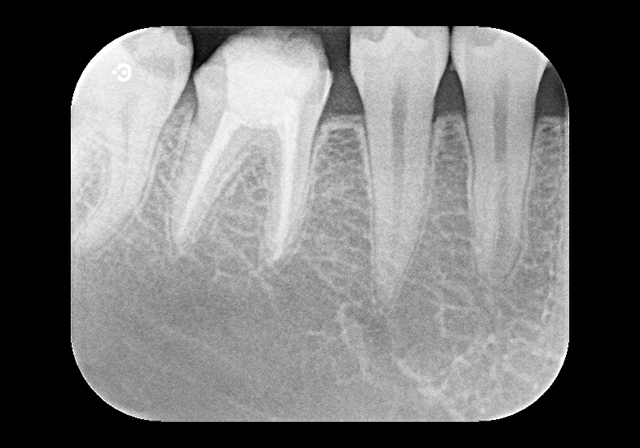

よく患者様から“神経をとった歯だからもう痛くならないですか?”との質問を受けます。その答えは“NO”です。実際に歯の根管はこのような複雑な形態をしています。この治療をおろそかにしてしまうと、根管に残った神経の残骸など炎症物質により、次は化膿して急激な痛みを引き起こすことがあるのです。

そのため、治療には時間もかかりますが、当院では様々な器具や取り組みを行い、再治療の可能性をできる限り少なくするよう、神経の治療(根管治療)を精密に行えるように努めております。